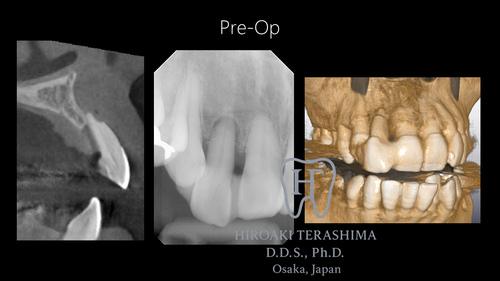

右上2番:根尖まで骨吸収、動揺度3、隣在歯と固定されていた状態

本症例は、術前から骨吸収と歯肉退縮を伴うタイプⅢ症例であり、 前歯部インプラント治療の中でも非常に難易度の高いケースです。![]()